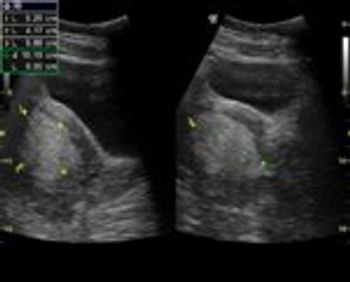

These are ultrasound images from a 2nd trimester pregnancy.